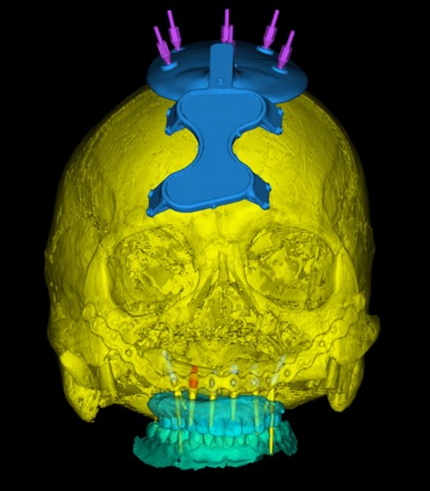

针对该患者的病情特点,杜良智主任团队联合西安交通大学第一附属医院神经外科李奇副主任医师经过多次会诊、反复确认,决定选择最靠近术区、最易实现和最安全可靠的颅骨来固定手术机器人工作标记物。并在术前借助数字化手段建立虚拟患者,模拟手术方案,反复验证可行性,确保最安全、最理想的种植修复效果。

在手术中,李奇副主任医师顺利在患者颅骨外固定手术标记物,拍摄螺旋CT后确认固定标志物的钉子穿透颅骨第一层骨皮质到达第二层骨髓腔,位置精准。麻醉科王智主任在患者清醒状态下进行了经鼻纤支镜麻醉,仅用时不到15秒一次成功,保证患者插管时血压和心率平稳。随后,将术前CT、术前规划、患者颅颌骨位置及机器人机械臂进行配准标定。杜良智主任团队通过机器人亚毫米级的定位方式,精准控制避开固定腓骨的钛板和钛钉,用时三小时,顺利将6颗种植体植入规划位置,确保种植体按预设位置准确就位,为后期修复上颌缺失牙列打下基础。